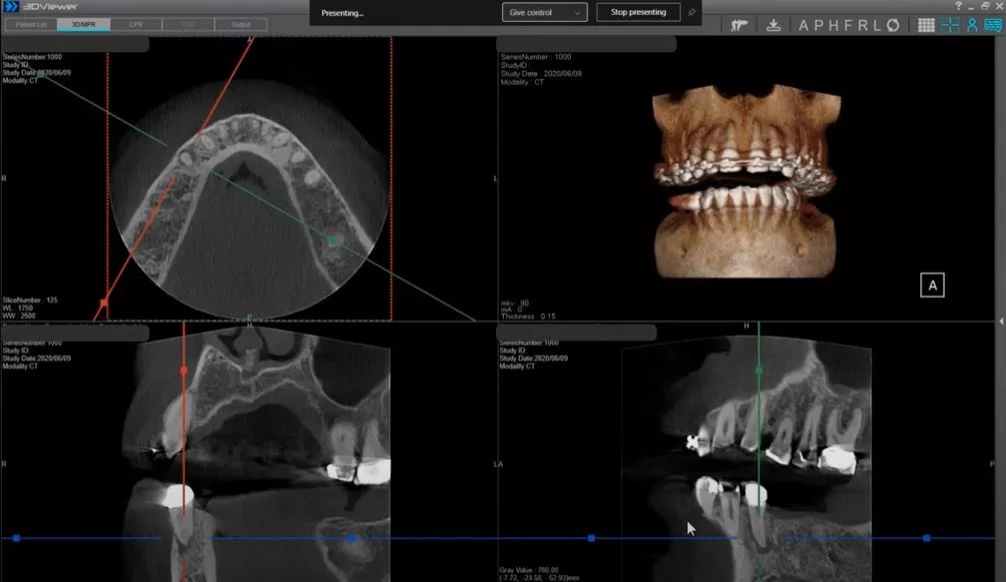

Given this fact, we are going to focus our discussion on this very common application. There are a host of different ways that a Cone Beam system can assist with implant planning. However, one of the most fundamental is providing visibility into the cross-sectional view of the location of the implant. In 2012, the AAOMR published a position paper recommending that cross-sectional imaging be used for assessment of all dental implant sites. Cone-beam Computed Tomography (CBCT) is the cross-sectional imaging method of choice. The cross sectional view provides critical information that cannot be gained from any purely 2D modality. The example below shows the cross sectional view.